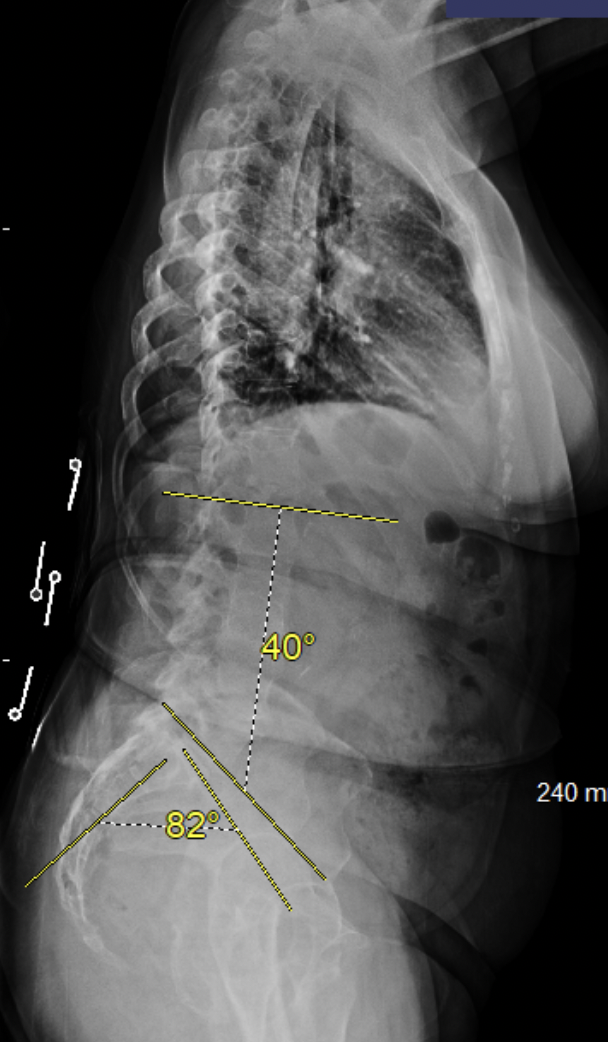

Rachis Déformatif

La chirurgie du rachis déformatif est une discipline complexe, qui demande une expertise approfondie et une expérience acquise au sein de grands centres spécialisés auprès des meilleurs experts en chirurgie des déformations vertébrales.

Mon parcours m’a permis de développer une maîtrise complète de l’équilibre sagittal, domaine clé pour la correction des scolioses de l’adulte, des spondylolisthésis ou des déformations sévères nécessitant parfois des ostéotomies vertébrales.

Cette expertise s’accompagne d’une rigueur particulière dans la planification préopératoire et le suivi postopératoire, essentiels pour assurer une correction durable, un alignement harmonieux et une récupération fonctionnelle optimale.